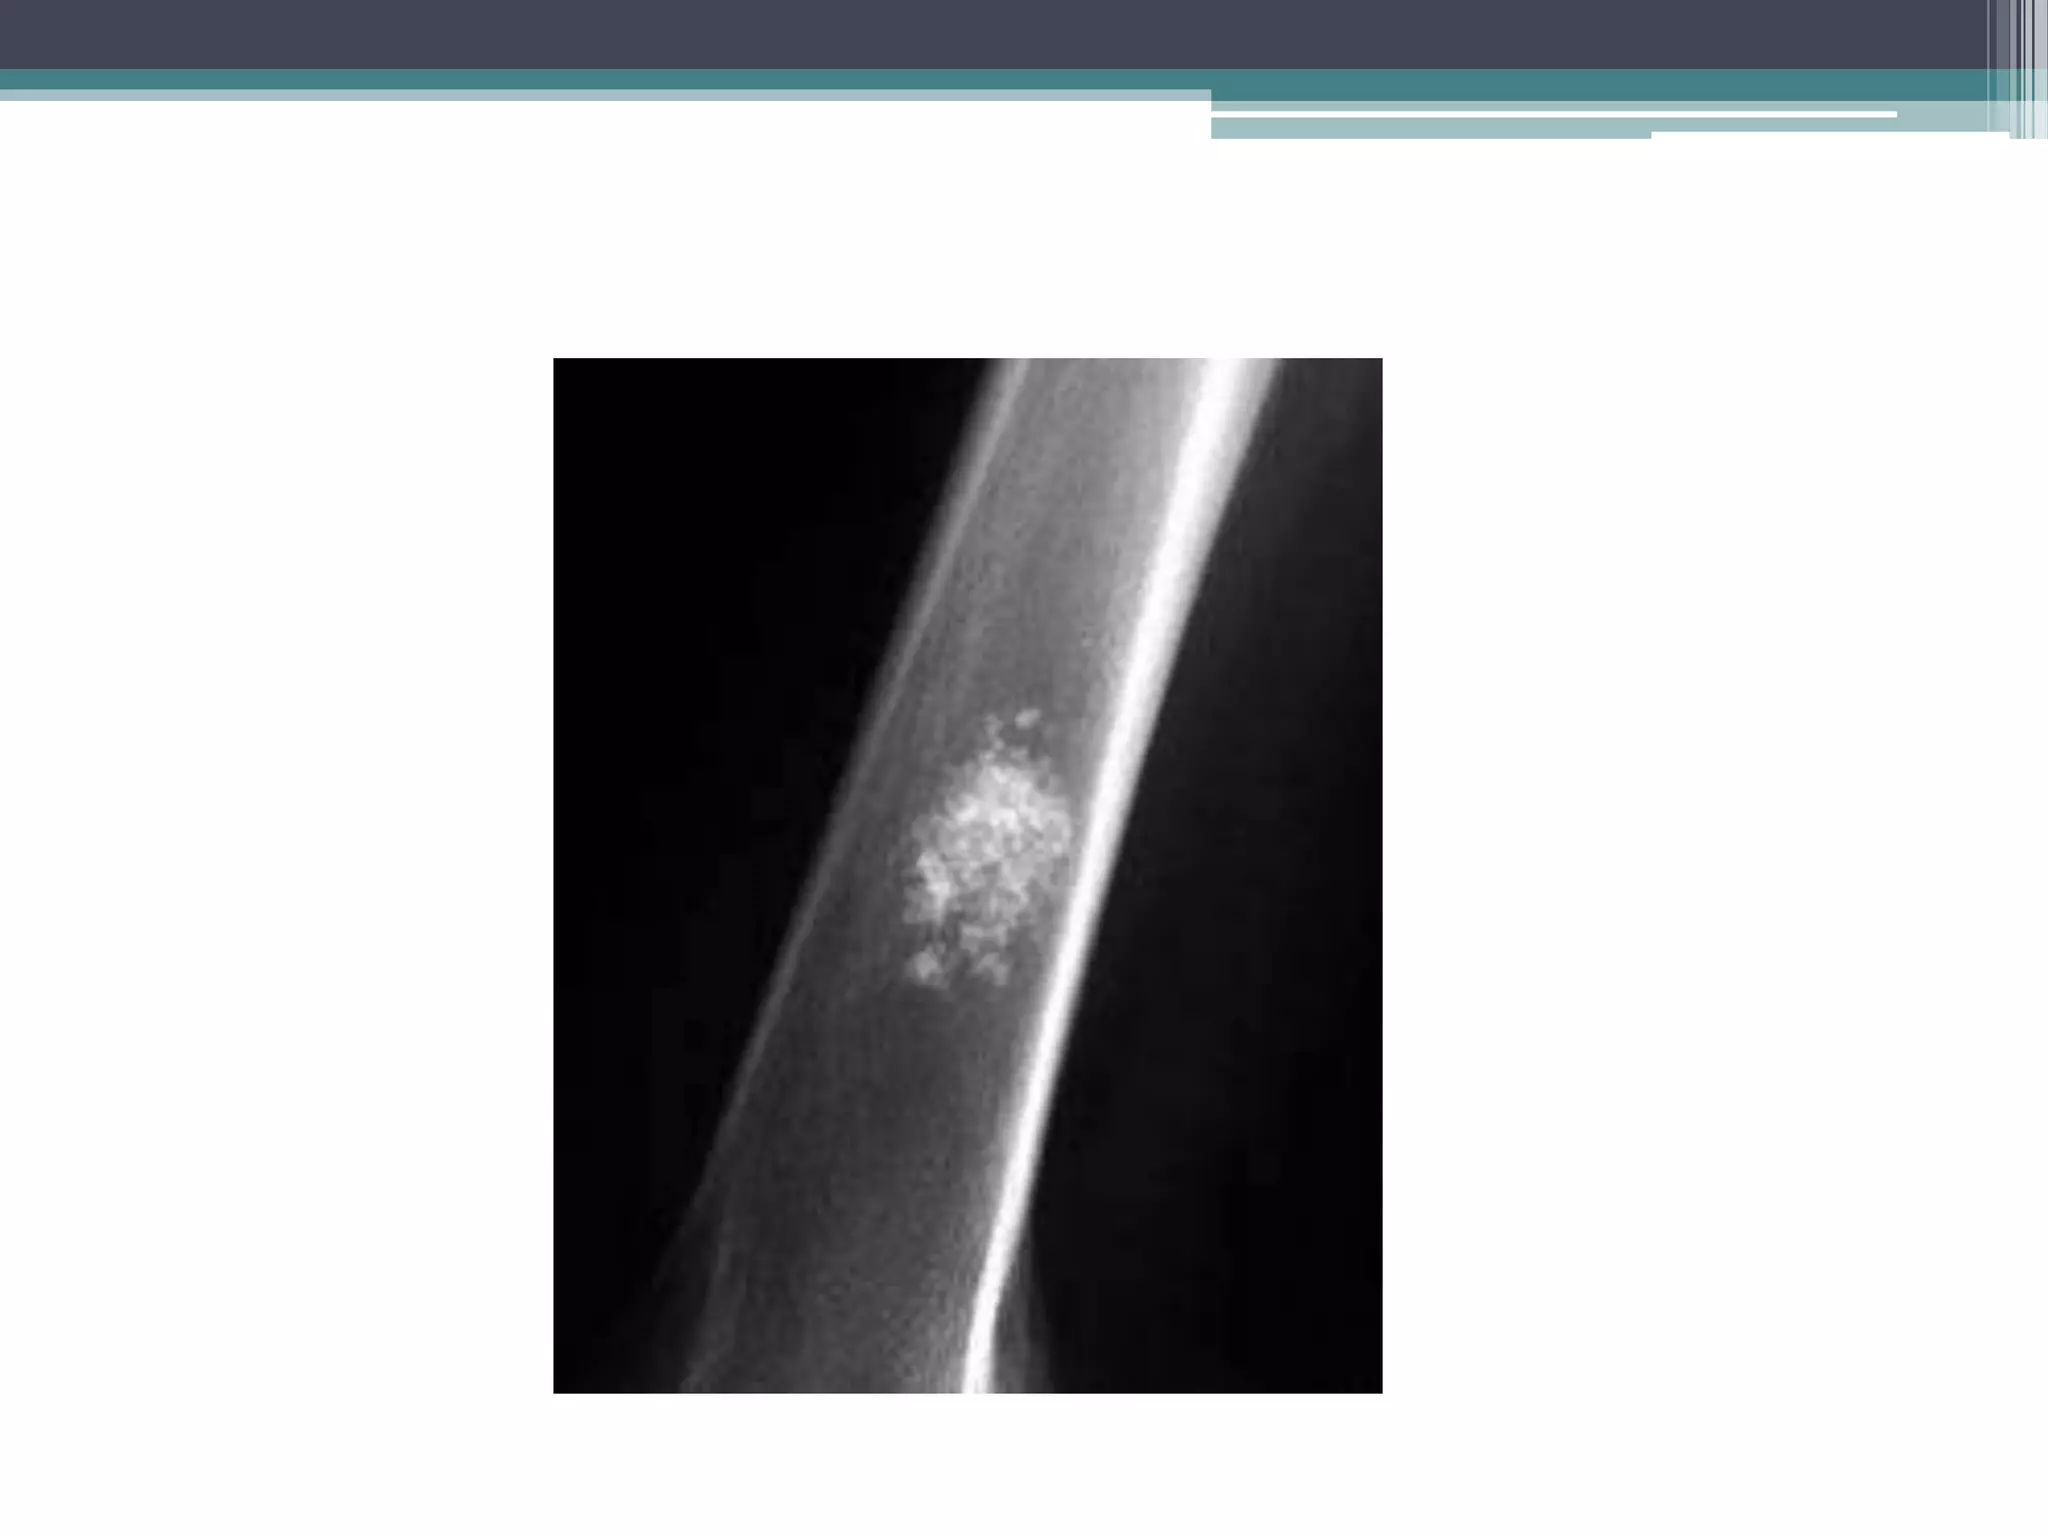

Small nidus <1 cm round oval in

shape in diaphysis

Small nidus <1cm round oval in shape in diaphysis • Treatment: • is surgically cutting out of the entire tumor, particularly the central core, for a good outcome